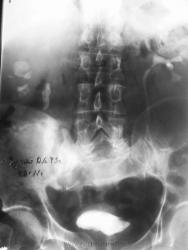

Качество достойно сожаления, участь ваша – сочувствия. Камни вижу в чашках нижнего полюса правой почки и в/3 правого мочеточника. А вот функции справа не вижу. Есть камень в мочевом пузыре.

Кроме того видны разрыв симфиза и правого крестцово-подвздошного сочленения. МОС шейки правого бедра.

Показалось, что на 30-й и 60-й минуте в верхней группе чашечек контраст нарисовался. Решила взять на КТ, гематурия, а в проекции уретры тоже вроде камень. Да и в мочеточнике - просто глазам не верится, что 3-сантиметовый гигант сидит. Ну, и вот такие картинки получила. Видео завтра, мне с работы не загрузить.

В почке от 4 до 6 (плоховато видно)

Случай становится совсем нерядовым. Камней (видимых) КТ прибавила. В пр. мочеточнике 2 камня.